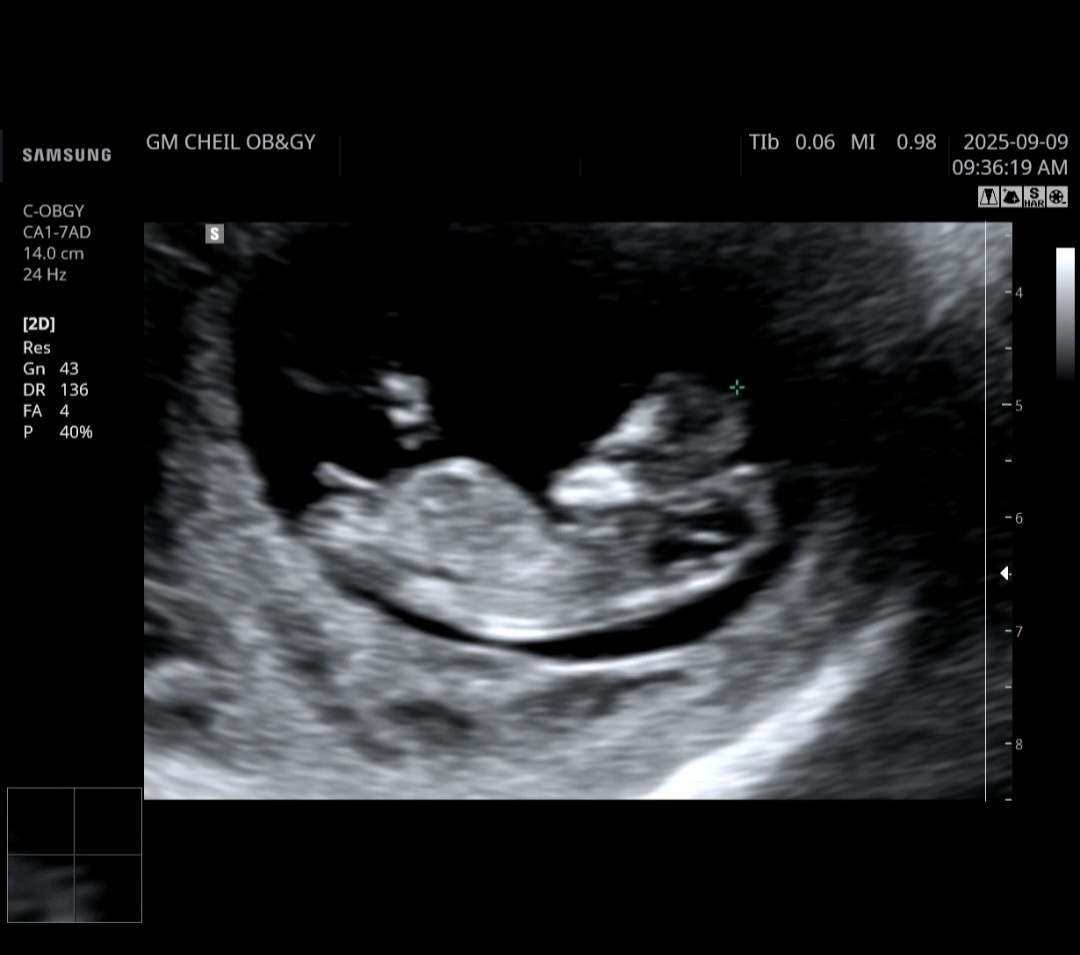

재미로 보는거라지만 혹시 각도법 고수님 계신가요 생식기가 유독 잘보이네요..ㅎㅎ

수평이루는거 보니 각도법으로는 딸같아보여요!